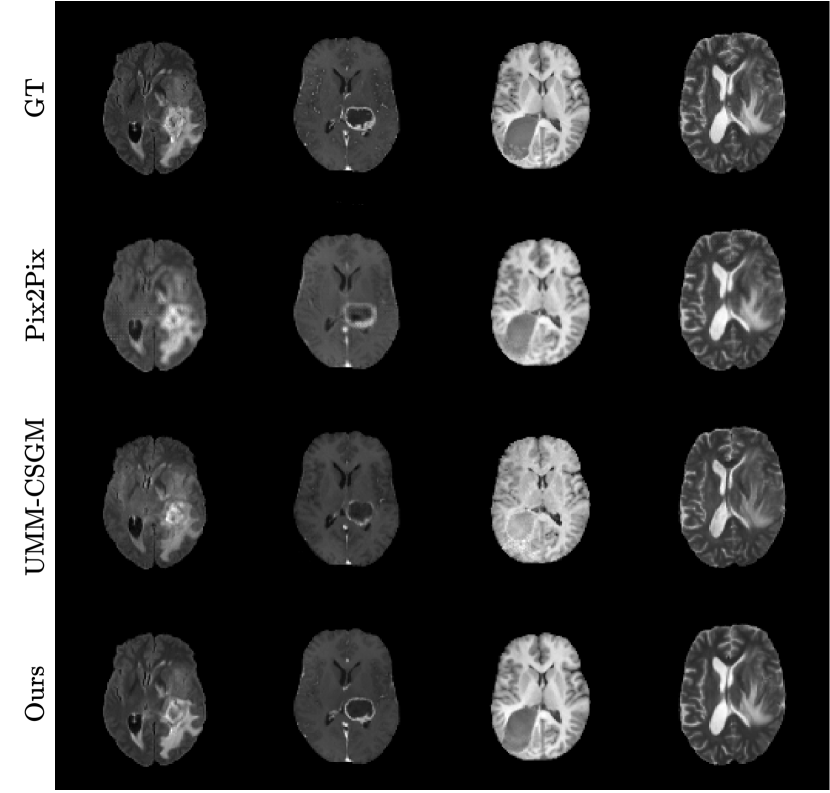

Refer to caption

Fig. 2: Comparison of translated MR sequences across different methods. Columns represent FLAIR, T1CE, T1, and T2 sequences (left to right).

3.3 Qualitative results

Figure 2 shows qualitative comparisons of missing sequence translations generated by our method and the two other comparative methods. Our approach demonstrates more realistic and fine-grained details in the overall brain structure, with particularly precise tumor boundary representation compared to UMM-CSGM. The textural contrast between gray and white matter is also better preserved. Pix2Pix, on the other hand, exhibits missing fine-grained details and limited brain structure clarity. Each translation by our model was achieved using the same instance, underscoring its adaptability for dynamically generating missing sequences with high fidelity. In Figure 3, we present adaptive translations from various input configurations. The first row shows ground truth, while red and green borders highlight the input and synthesized sequences, respectively. A clear trend is observed: the more input sequences available, the richer the IFFN’s unified representation, particularly improving tumor delineation in T2 sequences from the second-to-last rows. However, when fewer input modalities are provided, there is a tendency for random interpolation of tumor regions, especially without key modality pairs like FLAIR/T2 or T1/T1CE. This is visible in the second row’s T1CE, which improves as more input sequences are added. Despite fewer inputs, our method reliably captures enough information to translate missing sequences, illustrating the robustness of the IFFN. Additionally, our approach, treating 3D images as a sequence of 2D slices, can easily extend to 3D image translation by processing each slice and reconstructing the full 3D volume.